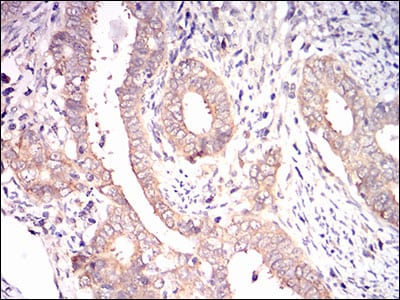

Immunohistochemical analysis of paraffin-embedded human cervical cancer tissues using EIF2A mouse mAb with DAB staining.